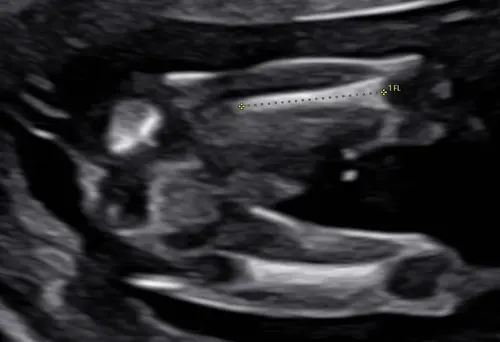

Maar inwendig krengen we dit beeld als eerste te zien, 2 benen met een puntje in het midden.. de verloskundige zei er niks over omdat wij het niet willen weten. Maar nu denk ik dus whaha zou het dan toch echt zo zijn!🤣🙈. We hopen stiekem zelf namelijk als gezin wel op een jongen!🥰

Dit beeld heb ik ook gezien 🤭 mijn gyno zei “we kijken deze echo niet naar het geslacht, ze hebben nu allemaal een verdikking” ja ammehoela 🤣 ik heb al een jongen dus herkende dit beeld direct 😜